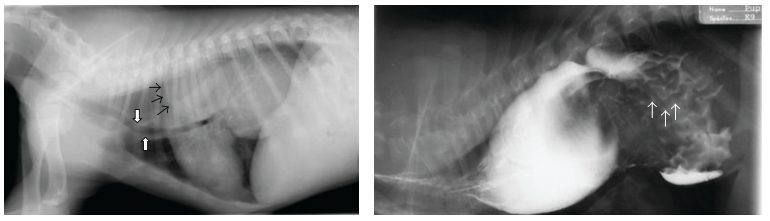

Likely diagnosis?

Gastroesophageal intussusception

Pollard, R.E. (2012) Imaging Evaluation of Dogs and Cats with Dysphagia. ISRN Veterinary Science 2012, 1–15